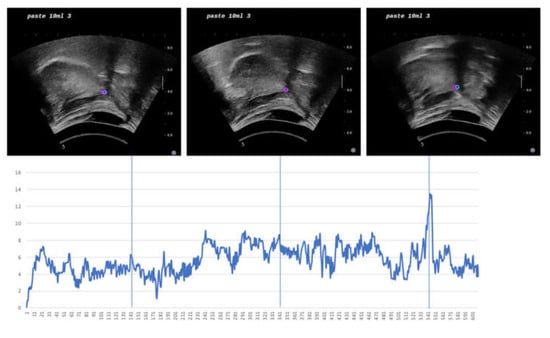

2.1. Ultrasound Swallowing Videos (USV) Dataset